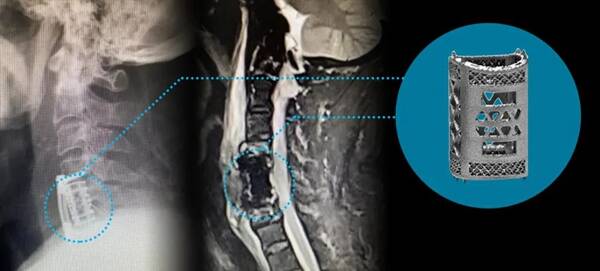

2022年9月22日,湘雅常德醫(yī)院脊柱外科陳芳田主任團隊成功完成一例頸椎間盤髓核切除術(shù)+C5椎體部分切除術(shù)+頸椎前路椎管減壓術(shù)+脊髓神經(jīng)根探查術(shù)+3D打印多孔型椎體融合器置入術(shù)。多孔型椎體融合器由湖南華翔醫(yī)療科技有限公司聯(lián)合南華大學附屬第一醫(yī)院脊柱外科團隊,采用金屬3D打印解決方案研發(fā)加工制造,獲得三類醫(yī)療器械許可證的選區(qū)激光熔融技術(shù)(金屬3D打印SLM技術(shù))骨科植入假體產(chǎn)品。

△金屬3D打印多孔椎體融合器

手術(shù)順利完成,患者術(shù)后肢體肌力明顯改善,疼痛麻木緩解。術(shù)后影像學檢查顯示:減壓充分,融合器位置良好?;颊邔κ中g(shù)效果非常滿意。

患者術(shù)后影像學資料

作為國家十三五重點研發(fā)成果的多孔型椎體融合器,是以鈦合金粉末(Ti6AI4V) 為原材料,是國內(nèi)首款采用3D打印選擇性激光熔融技術(shù)(SLM)成型,并獲得三類醫(yī)療器械許可證產(chǎn)品。

其椎體匹配上下終板的解剖角度,適配性強,完全滿足臨床需求。大植骨窗設(shè)計,促進植骨融合效果。結(jié)構(gòu)上采用仿骨小梁結(jié)構(gòu)設(shè)計,彈性模量與人體骨組織相近,可有效降低內(nèi)植入物的塌陷風險。其孔隙率80%±,孔徑結(jié)構(gòu)300μm±,絲徑200μm±,可為骨細胞的遷移增殖提供良好的空間環(huán)境,從而實現(xiàn)骨長入,完成骨整合,達到長期穩(wěn)固狀態(tài)。